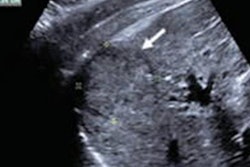

Current guidelines for screening for hepatocellular carcinoma recommend semiannual ultrasound of the liver in patients at risk. But two patient factors -- cirrhosis and large body habitus -- can reduce ultrasound's sensitivity for this purpose, which may translate to delayed diagnosis and increased mortality, the team wrote. A shortened MRI protocol has been proposed as a surveillance alternative, since the modality offers high sensitivity and specificity.